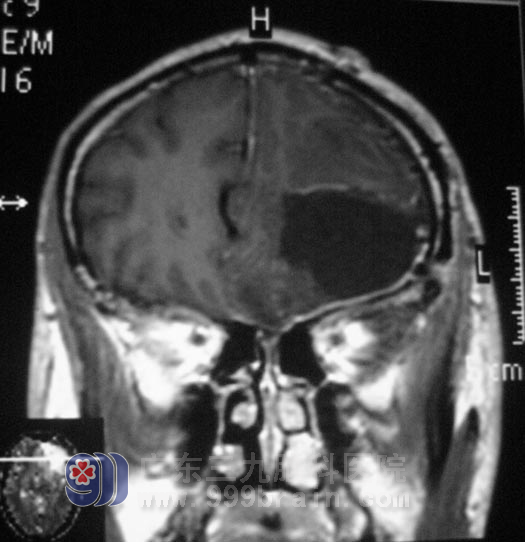

4月26日由 综合神经外科的 鲁明主任主刀,在全麻下行“左额叶、岛叶肿瘤切除术”, 术中导航定位,见左额部局部脑皮层黄色变性,肿瘤质软,呈灰白色,其间可见灰褐色成分,显微镜下将肿瘤及其表面变性脑组织一并切除。由于手术中对功能区进行了很好的保护,术前所担心的失语、偏瘫都没有出现。病理结果回报:(左额部)胶质母细胞瘤,WHO IV级。

现在的龙大爷恢复良好,等待后期的放疗。他又恢复了往日的开心和幽默。

手术后